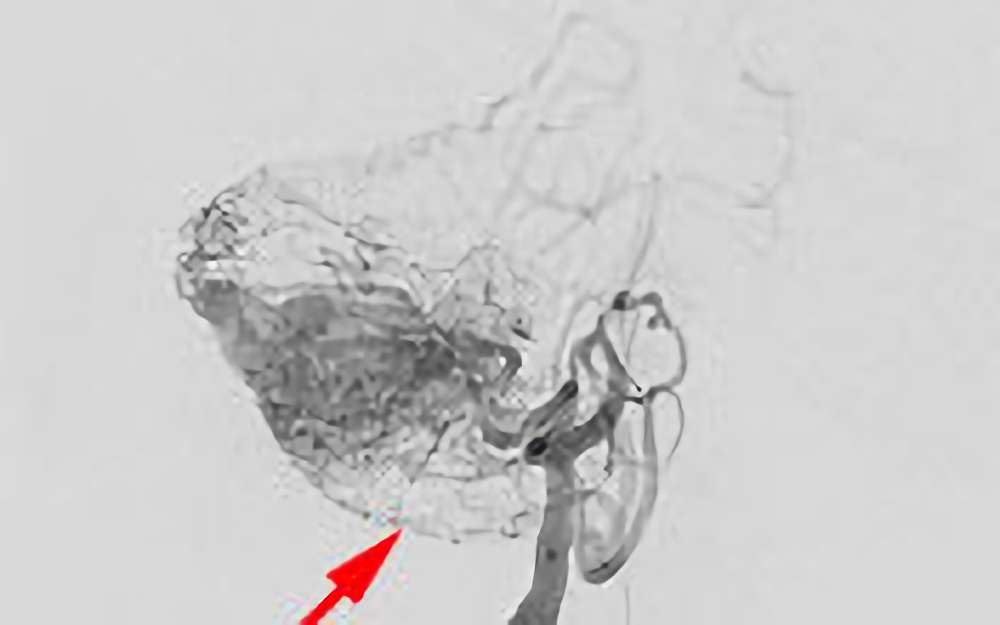

No.1620 手術前